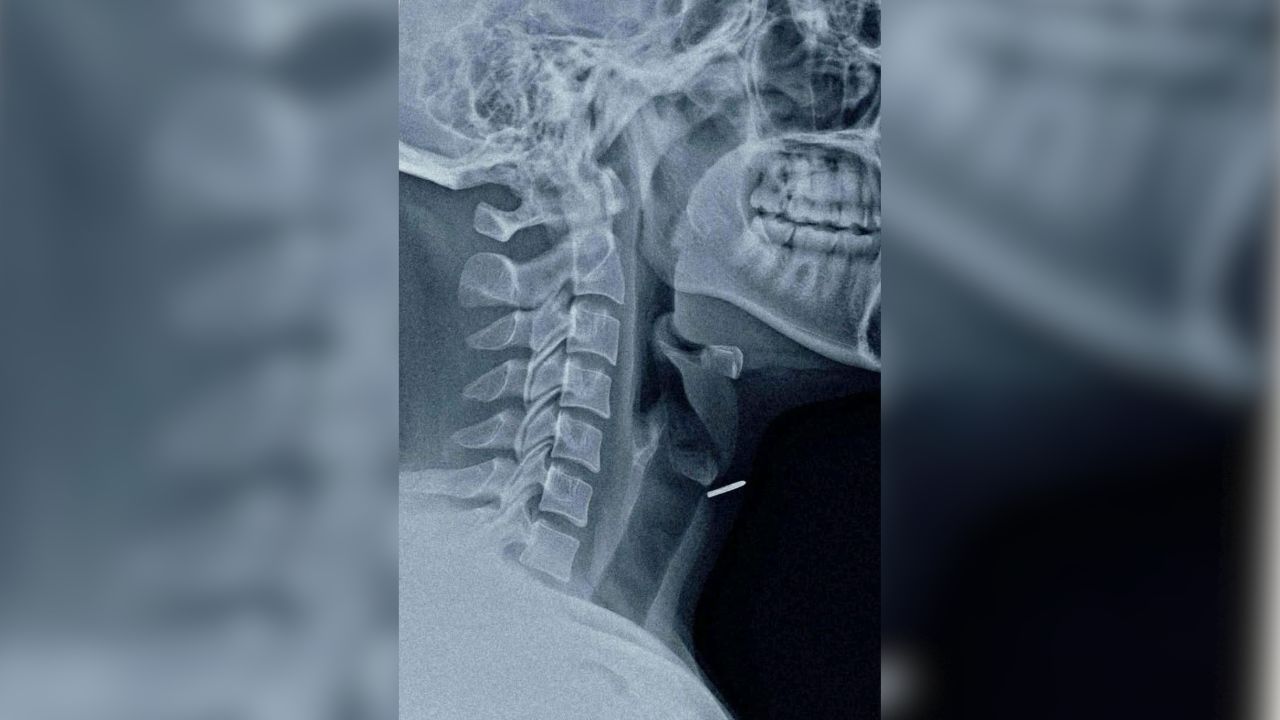

डाइनामाइट न्यूज़ संवाददाता को मिली जानकारी के अनुसार घायल युवक दीपू (उम्र 28 साल) को स्वशासी राजकीय चिकित्सा महाविद्यालय संबद्ध जिला अस्पताल मोतीपुर ओयल लाया गया। मरीज पहले से एक्स रे करा कर लाया था, जांच करने में पता चला कि कील सीधी थायरॉइड ग्रंथि में जाकर फंस गई है। बता दें कि थायरॉइड ग्रंथि श्वास नली के ठीक पास स्थित होती है। यह स्थिति अत्यंत गंभीर थी, यदि व्यक्ति थोड़ी सी भी लापरवाही करता तो उसकी जान भी जा सकती थी।

इस नाजुक स्थिति को गंभीरता से लेते हुए सहायक आचार्य ईएनटी सर्जन डॉ. मनोज शर्मा ने लोकल एनेस्थीसिया में ऑपरेशन किया और कील को सफलतापूर्वक बाहर निकाला। यह ऑपरेशन इतना जोखिम भरा था कि अगर डॉक्टर से भी कुछ गलती हो जाती तो व्यक्ति की जान जा सकती थी।

मामले को लेकर डॉ. शर्मा ने बताया कि यह मामला दुर्लभ और चुनौतीपूर्ण था। कील श्वसन नली के एकदम पास में थी। ऑपरेशन के समय उन्हें काफी सावधानी बरतनी पड़ी ताकि कील निकालते समय कहीं श्वास नली में ना चली जाए।